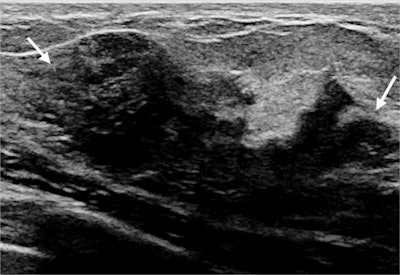

Targeted ultrasound scans identified a sonographic correlate to the palpable lump for 66% of women. A little more than half of these women had findings categorized as benign or probably benign, with cysts, inflammation or infectious changes, and galactoceles representing the most common benign findings.

An additional 53 women were recommended for biopsy due to a BI-RADS 4 or 5 lesion on the targeted ultrasound scan. Of these women, five were diagnosed with invasive ductal carcinoma. Mammography identified seven additional suspicious lesions but no additional cancers.